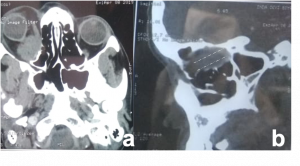

| Lesion | Age/Sex Predeliction | Clinical Presentation | Imaging Findings | Other features | Image |

| Thyroid Eye Disease[16] | Young adults; Female > Male | Axial Proptosis, Redness, watering, lateral flare, lid retraction, photophobia.

Restrictive myopathy |

CT- spindle enlargement of EOMs occurs with relative normal tendinous insertion (coca-cola bottle sign).

MRI - Bulky EOMs are isointense on T1, slightly hyperintense on T2W images and show enhancement. |

Most frequent involvement IR>MR>SR>LR. Superior Ophthalmic Vein may be enlarged due to apical compression | Axial and coronal section of non-contrast CT images of orbit showing three different patterns of TED. a) Bilateral fusiform enlargement of the extraocular muscles sparing the tendinous insertion with posterior crowding (orange stars) b) Bilateral fusiform enlargement of the extraocular muscles sparing the tendinous insertion along with increased orbital fat. c) Bilateral increased orbital fat (denoted by increase of hypodense areas of fat attenuation). EOM appears normal. |